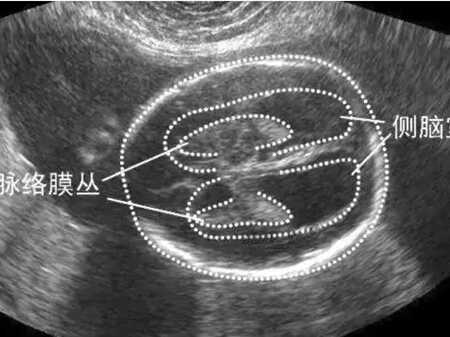

透明隔腔在妊娠期的正常宽度为≤1.0cm,从怀孕10―12周时开始发育。如果妊娠中超声检查显示透明隔腔宽度大于1.0cm,有可能是透明隔囊肿,在出生时后可表现出头痛、昏厥、癫痫、精神障碍或神经症等精神异常。侧脑增宽是孕中期后测量胎儿侧脑室宽度的超声检查结果,侧脑室正常宽度≤10mm,如果侧脑室宽度大于10mm就称为侧脑室增宽,大多数时候是由于胎儿中枢神经系统异常,也就是胎儿脑中线发育结构异常及胎儿脑脊液过多导致,也有可能是染色体异常或病毒感染引起全身其它系统异常导致的一种颅内表现。脑室宽度大于15mm就是脑积水,侧脑室增宽1.5㎝就是脑室扩大,宽度越宽程度越重。妊娠中超声检查显示有侧脑室增宽,程度严重的不建议继续妊娠。增宽程度轻微,医生建议保留胎儿的,在出生后应尽量检查明确病因,若继续存在明显的脑室增宽,需要到小儿科尽早做检查治疗。妊娠期轻度的侧脑室增宽,基本上百分之九十的胎儿神经发育正常,需要进一步检测智力发育,出生后的智力发育和做出治疗的时间早晚有关系。有严重的侧脑室增宽的胎儿,在神经发育上差于正常及轻微增宽的胎儿。

怀孕中胎儿超声检查显示侧脑室有增宽的,也有可能是生理积液,是生长发育中脑脊液循环功能还不完善导致的。随着胎儿逐渐增长,神经系统进一步发育,情况就有可能出现好转。可以按照医生安排,再次复查四维彩超,随时观察胎儿侧脑室增宽的情况,也可以进一步做唐筛、无创或羊水穿刺,以确定胎儿存不存在染色体异常或病毒感染。胎儿的侧脑室正常在1㎝以下,出现增宽多是脑脊液过多引起。大多数时候,不存在其它病变情况的,在孕晚期会自动吸收。只要继续复查时确定没有继续增宽,没有就不必过于担心了。侧脑室增宽太多的,怀疑胎儿存在脑积水的,只需要检查胎儿有没有脊柱裂就能准确判断是否真的是脑积水。